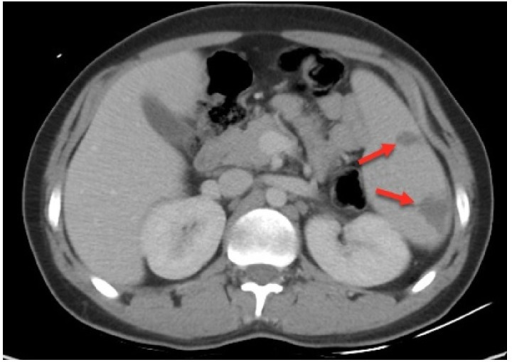

What's the Diagnosis?